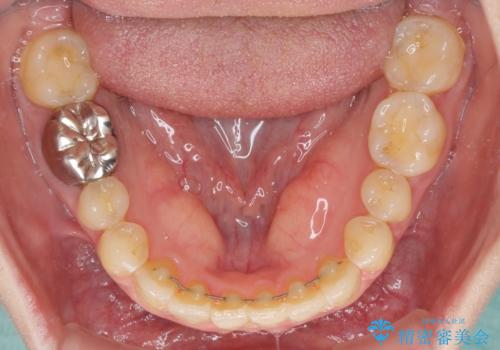

- 前歯のデコボコを治したいとのことで来院された患者様です。

上下顎ともに歯列全体の後方移動とIPR(歯と歯の間を削る)によってデコボコが解消するように設計し、インビザラインにより治療を行うこととしました。

1日22時間の装着時間をほとんど達成することができず、治療には当初予定の2倍以上の期間を要することとなりました。